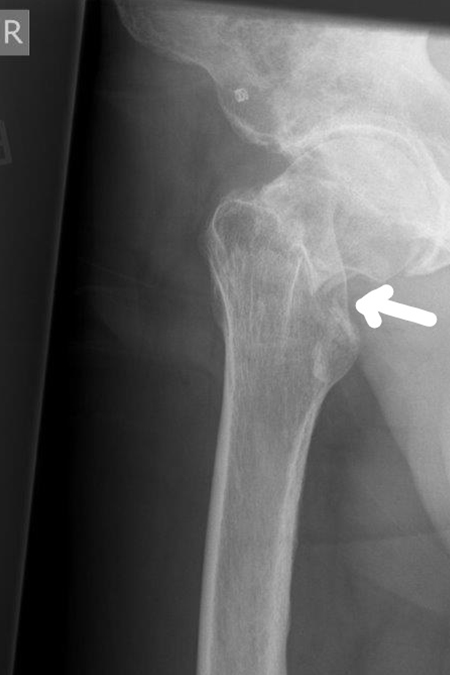

DIE FOLGENDEN BILDER ZEIGEN BEISPIELHAFT RÖNTGENERGEBNISSE NACH OPERATIVER BEHANDLUNG IN UNSERER ABTEILUNG:

Deutliche Knochenstufe am Schenkelhals

03/2021 – 76 jährige Frau mit wahrscheinlich durch Osteoporose bedingtem Bruch des Schenkelhalses rechts. Es wurde ein zementierter Standardschaft verwendet, der eine gleichmäßige Krafteinleitung in den Knochen des Oberschenkels gewährleistet.  Verlauf sonst unkompliziert mit guter Gelenkfunktion bereits 2 Monate nach Operation. Die Osteoporose sollte durch Bewegung und Medikamente über einen längeren Zeitraum behandelt werden.

rechtsseitige Schenkelhalsfraktur